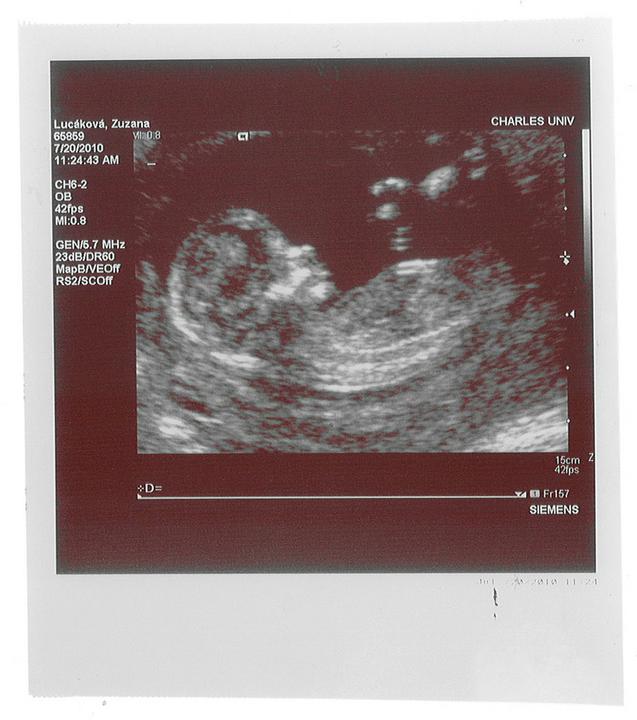

Už jen šest dní a pádíme na velký UZ! Tak copak myslíte, ukáže nám mimíšek, jestli bude Johanka nebo Štěpán? 🙂

Holčička? Chlapeček? Holčička? Chlapeček? ...zítra už možná budeme vědět! 🙂

Týýý jo...se mi zdá, že dny jsou pořád delší a delší 🙂 příští úterý jdeme na UZ, tak jsme zvědaví-prý vypadám na chlapečka, ale přáli bychom si o trošičku více holčičku, tak snad...